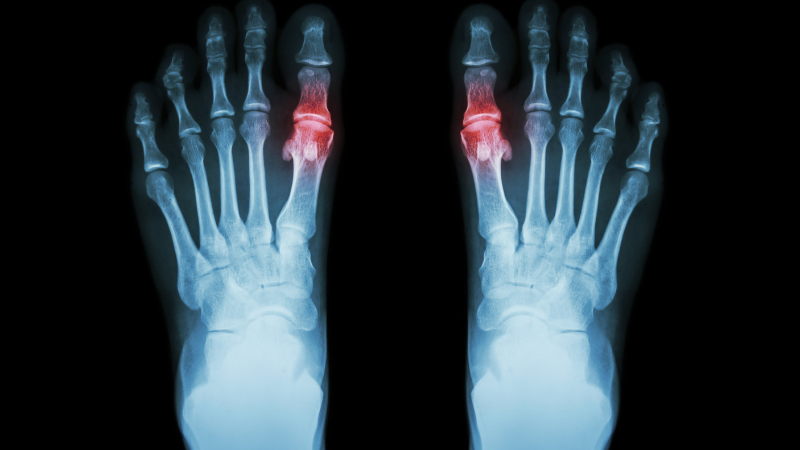

Normalerweise liegt die Harnsäurekonzentration im Blut zwischen 3,5 und 7,2 mg/dl. Steigt der Harnsäurespiegel über diesen Bereich, können sich Harnsäurekristalle in den Gelenken ablagern. Diese Kristalle lösen schmerzhafte Entzündungen aus, die als akuter Gichtanfall bekannt sind. Besonders häufig sind die Gelenke der Zehen, aber auch andere Gelenke wie Knie oder Finger können betroffen sein. Die Ablagerung von Harnsäurekristallen ist das zentrale Merkmal dieser Stoffwechselerkrankung und führt zu den typischen Symptomen wie plötzlichen Schmerzen, Schwellungen und Rötungen.

Ein akuter Gichtanfall äußert sich häufig in schmerzhaften Entzündungen des großen Zehengelenks. Die Symptome umfassen typischerweise:

- starke Schmerzen

- Rötung

- Schwellung des betroffenen Gelenks und Gelenkschmerzen. Diese Anfälle treten oft plötzlich und meist nachts auf, was die Schmerzen noch intensiver erscheinen lässt. Es gibt verschiedene Formen des Anfalls, wobei besonders der akute Gichtanfall (Gichtarthritis) mit plötzlicher Entzündung einzelner Gelenke wie Rötung, Schwellung und Schmerzen im Mittelpunkt steht. Der Schmerz kann dabei sehr belastend sein und auch die Zehen betreffen.

Häufig werden Gichtanfälle durch schwere Mahlzeiten oder Alkoholkonsum ausgelöst. Interessanterweise sind bei akuten Gichtanfällen nicht immer erhöhte Harnsäurespiegel im Blut nachweisbar, obwohl die Entzündungswerte erhöht sind. Auch die Knie können häufig von Gicht betroffen sein, was zu Schmerzen und Schwellungen in diesen Gelenken führt. Diese widersprüchlichen Befunde können die Diagnose erschweren, weshalb eine gründliche Untersuchung notwendig ist.

Moderne bildgebende Verfahren wie die Dual-Energy-Computertomographie können Harnsäureablagerungen früher erkennen als herkömmliche Röntgenbilder, die erst Veränderungen zeigen, wenn sich größere Ablagerungen gebildet haben. Blutuntersuchungen, Gelenk-Sonographie und Röntgenuntersuchungen sind daher wesentliche Bestandteile der Diagnose. Die medizinische Diagnostik spielt hierbei eine zentrale Rolle, insbesondere Fachärzte für Innere Medizin sind für die genaue Abklärung und Behandlung von Gicht besonders qualifiziert.